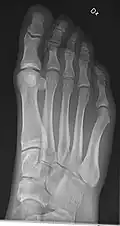

Extremities

A projectional radiograph of an extremity confers an effective dose of approximately 0.001 mSv, comparable to a background radiation equivalent time of 3 hours.[16]

• Hand - DP and Oblique

• Fingers - DP and Lateral

• Thumb - AP and Lateral

• Foot / Toes - Dorsoplantar, Oblique and Lateral.[19]